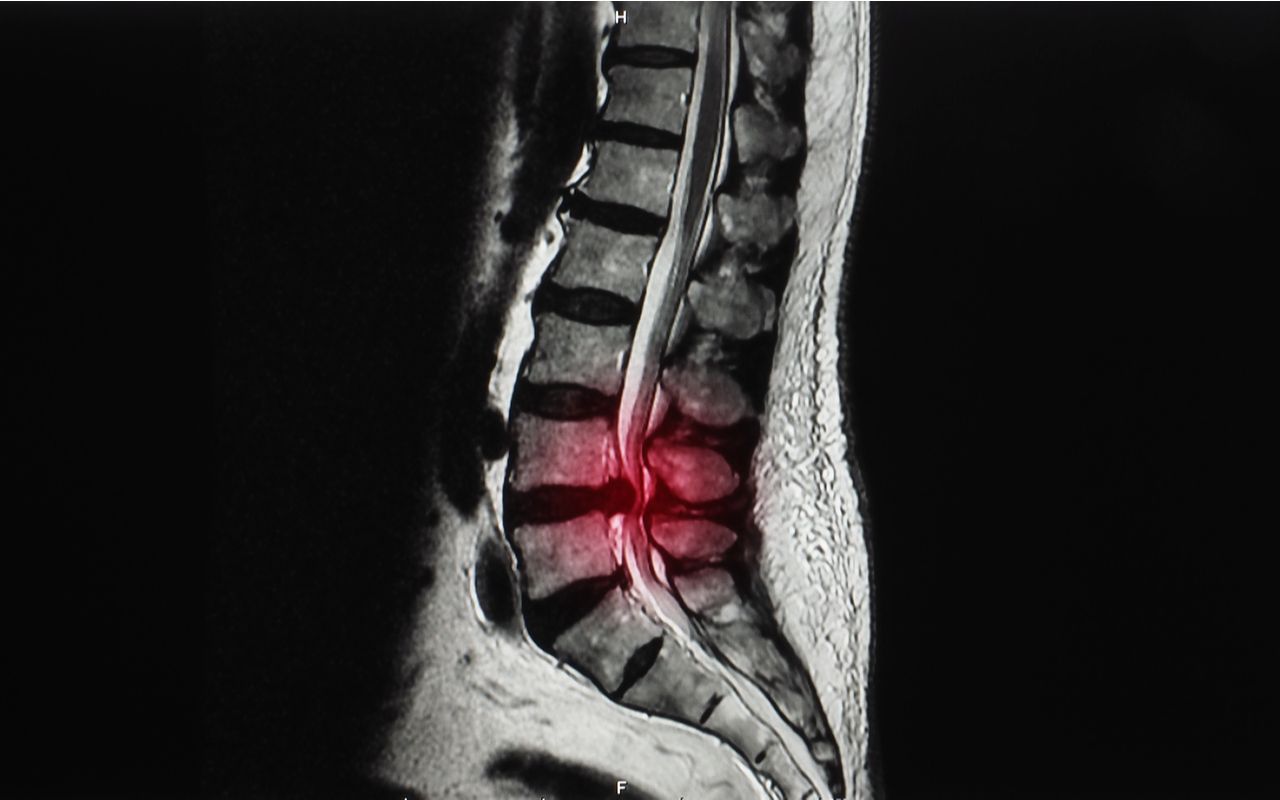

Construction’s Big Pain: How Imaging May Misdirect Care for Lower Back Soreness

Back injuries are the most common injury in construction, but despite billions of dollars spent on treating back pain, MRIs and other tests often fail to provide